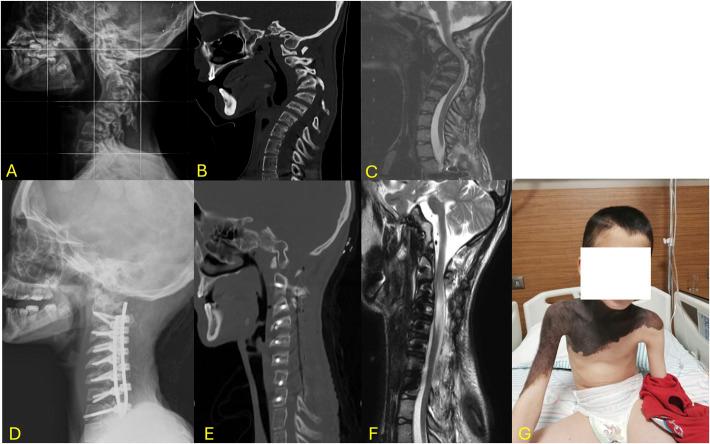

在伴有神经纤维瘤病1型(NF1)的儿童颈椎后凸畸形中,采用颈椎椎弓根螺钉固定而非侧块固定进行一期矫正的手术结果:一项至少随访2年的回顾性研究

Surgical Outcomes of Single-Stage Correction Using Cervical Pedicle Screw Fixation Rather Than Lateral Mass Fixation in NF1-Associated Pediatric Cervical Kyphosis: A Retrospective Study with a Minimum 2-Year Follow-Up.

Neurofibromatosis type 1 (NF-1) can cause severe kyphosis in the cervical vertebrae. There is no consensus on the optimal surgical treatment for this rare condition, although long-segment fixation and combined approaches are generally preferred. To our knowledge, this study is the first to report the clinical outcomes of patients with NF-related cervical kyphosis who underwent stand-alone posterior pedicle fixation surgery.

METHODS

The outcomes of 14 patients who underwent surgery using the pedicle screw were retrospectively examined between 2015 and 2022. Only patients with at least 2 years of follow-up were included. For each patient, the following parameters were recorded and evaluated at 1 month postoperatively and at the end of the follow-up period: cervical lordosis (CL), local kyphosis angle (LKA), T1 slope, cervical sagittal vertical axis, visual analog score for neck pain, modified Japanese Orthopedic Association score, and Neck Disability Index. Complications, surgical duration, blood loss, levels of instrumentation, and length of hospital stay were also recorded.

RESULTS

In terms of radiographic parameters, all patients achieved lordosis, with the cervical LKA improving from an average of 76.7° preoperatively to an average of 20.4° in the early postoperative period. At the 2-year follow-up, the postoperative CL significantly improved compared with preoperative values (p < 0.001) with only approximately 4° correction loss. Moreover, by the end of the follow-up, all postoperative symptoms showed improvement compared with the preoperative symptoms. The average surgical duration was 211.86 ± 49.83 min. During the follow-up, junctional kyphosis was observed in 4 patients all of whom required revision surgery. C5 palsy was detected in 3 patients. Infection-related complications occurred in 6 patients, with wound infection in only 1 patient.

CONCLUSION

Cervical pedicle screw fixation is an effective treatment for NF-1-related cervical kyphosis. Although this technique is considered difficult and dangerous to apply by several spine surgeons, it exerts a positive effect on clinical improvement and provides optimal correction.

1型神经纤维瘤病(NF-1)可导致严重的颈椎后凸。对于这种罕见病症的最佳手术治疗方法尚无共识,尽管通常更倾向于采用长节段固定和联合手术方式。据我们所知,本研究是首例报告接受单纯后路椎弓根固定手术的NF相关颈椎后凸患者的临床结局。

方法

回顾性分析2015年至2022年间14例行椎弓根螺钉手术患者的结局。仅纳入随访至少2年的患者。对每位患者,在术后1个月和随访期末记录并评估以下参数:颈椎前凸(CL)、局部后凸角(LKA)、T1斜率、颈椎矢状垂直轴、颈部疼痛视觉模拟评分、改良日本骨科协会评分和颈部功能障碍指数。还记录并发症、手术时长、失血量、内固定节段数和住院时间。

结果

在影像学参数方面,所有患者均实现了前凸,颈椎LKA从术前平均76.7°改善至术后早期平均20.4°。在2年随访时,术后CL与术前值相比显著改善(p < 0.001),仅约4°的矫正丢失。此外,到随访结束时,所有术后症状与术前症状相比均有改善。平均手术时长为211.86 ± 49.83分钟。随访期间,4例患者出现交界性后凸,均需翻修手术。3例患者检测到C5麻痹。6例患者发生感染相关并发症,仅1例患者出现伤口感染。

结论

颈椎椎弓根螺钉固定是治疗NF-1相关颈椎后凸的有效方法。尽管该技术被一些脊柱外科医生认为应用困难且危险,但它对临床改善有积极作用并提供了最佳矫正。